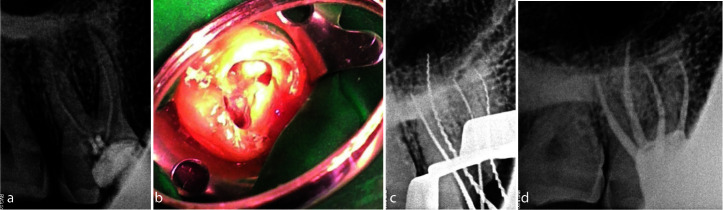

An in-depth understanding of the anatomical variations of maxillary molars is essential for endodontic success. Unlike the maxillary second molars, the presence of a second palatal root is uncommon in the first maxillary molar. This case report describes two cases of non-surgical management of maxillary molars with extra palatal roots. Careful clinical examination, knowledge of the internal anatomy, and the use of advanced radiographic modalities like cone beam computed tomography (CBCT) can reveal the presence of variations in the internal and external anatomy of any tooth. Therefore, for nonsurgical as well as surgical management clinicians should always watch out for any deviations in a tooth and utilize all the available tools to diagnose and manage them successfully.